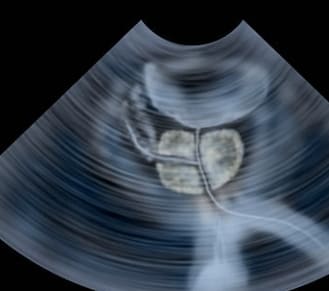

- 진단은 의사가 문진, 신체검사, 소변검사, 혈액검사, 초음파검사 등을 통해 진행합니다.